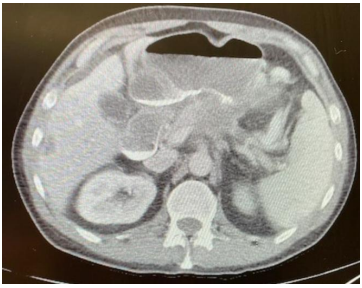

The procedure involved passing a guide wire beyond the obstruction using a gastroscope using contrast dye under fluoroscopy. Then the 8.5 Fr nasobiliary cannula (Boston Scientific, Marlborough, MA) was passed over the guide wire beyond the luminal obstruction and to achieve that a balloon extraction catheter (Boston Scientific, Marlborough, MA), was used since the length of the cannula was not adequate (Figure 3). Then using a linear array echoendoscope (Olympus, Center Valley, PA) from the stomach a suitable jejunal segment beyond the obstruction was selected by passing the diluted contrast agent through the cannula. Using both the images from the echoendoscope and fluoroscope 20 mm x 10 mm lumen apposing metal stent (LAMS) Axios (Boston Scientific, Marlborough, MA) was successfully deployed (Figures 4, 5, and 6).

Figure 4. Successful deployment of LAMS

Figure 5. Successful deployment of stent

Figure 6. Successful deployment of stent